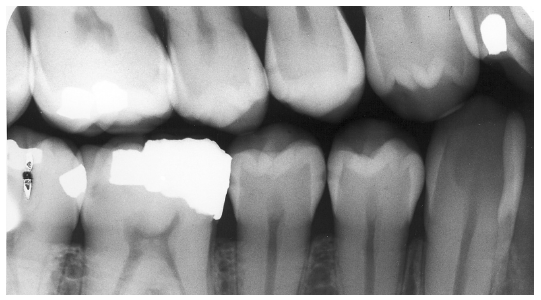

Figure 1 is a molar bitewing radiographic image that discloses a defective abutment restoration on tooth #4. The restoration ends short leaving open margins.

Figure 1 - Defective Restoration; Abutment Tooth #4

Figure 1